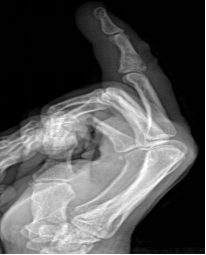

痛风

嘌呤代谢紊乱,以体液、血液中尿酸增加及尿酸盐沉着于各种间叶组织内引起炎症反应

好发于男性,发病高峰40-60岁

以第1跖趾关节最为多见

早期周围软组织肿胀,出现局限骨质硬化,晚期关节面边缘出现囊状、穿凿状骨质缺损,关节间隙可变窄,关节面不光整,晚期骨赘形成可使骨端增大

68Y,M